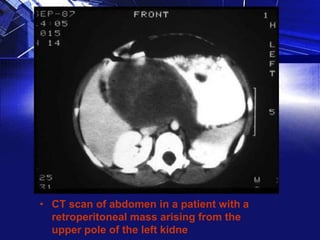

• CT scan of abdomen in a patient with a

retroperitoneal mass arising from the

upper pole of the left kidne